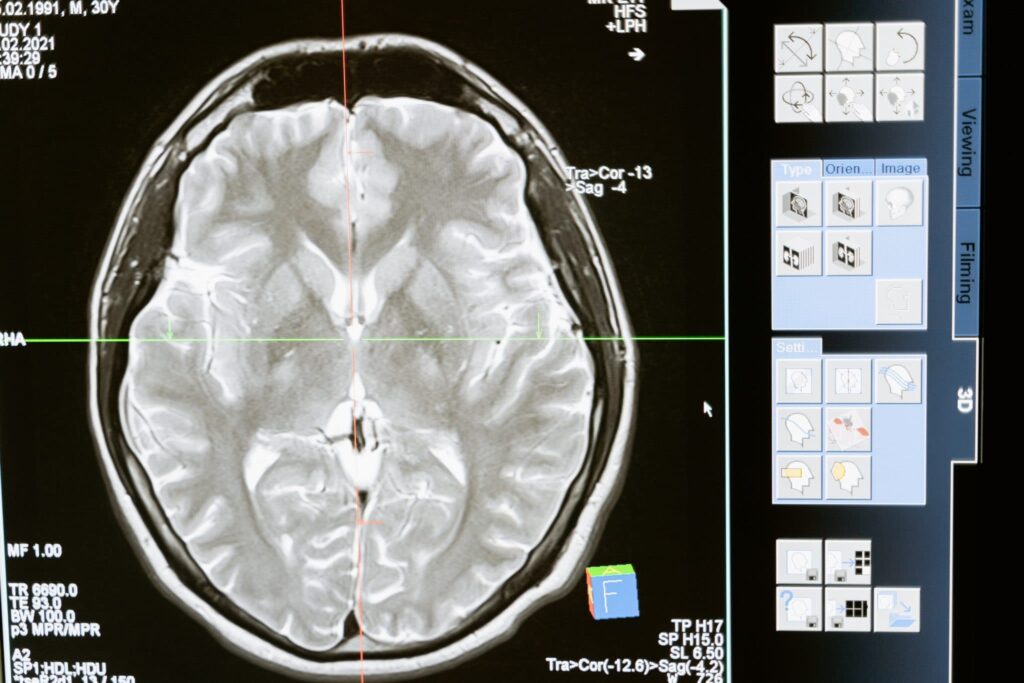

Neurologiset oireet katoavat monilla potilailla ajan myötä. / Mart Production